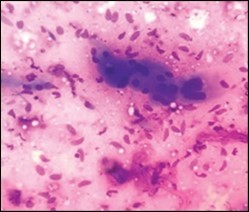

Histological Elucidation

On gross examination, a tan coloured, gritty nodule, confined to the sternocleidomastoid muscle is delineated. Characteristically, smears obtained by fine needle aspiration cytology are composed of bland appearing, plump or normal fibroblasts and proliferating fibroblasts with an admixture of degenerative, atrophic skeletal muscle cells, giant myocytes with several nuclei, scattered, bare, bland nuclei or cells with fragmented, wispy cytoplasm and parallel aggregates of fibroblasts. The background is clear and devoid of cellular or nuclear debris. Sheets of spindle-shaped fibroblasts, atrophic muscle fibres and regenerating, multinucleated muscle giant cells are intermingled with the fibroblastic component 5, 6.

Figure 4.Fine needle aspiration cytology of fibromatosis colli delineating aggregates of plump, spindle-shaped cells admixed with fibroblasts, fibro-connective tissue fragments and intermingled red cell extravasation 11

Figure 5.Fine needle aspiration cytology of fibromatosis colli exhibiting aggregates of spindle- shaped cells, plump fibroblasts, fibro-connective tissue fragments and a clear background with minimal red cell extravasation 12.